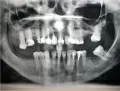

Был сделан панорамный снимок! Не могли бы вы подсказать, на какие зубы стоит обратить снимание?

• Не так все и плохо! Необходимо удалить обе нижние восьмерки (38, 48) и перелечить 46, 36 зубы, так как проглядывается некачественная пломбировка каналов, что в последствии повлияет на состояние зуба.